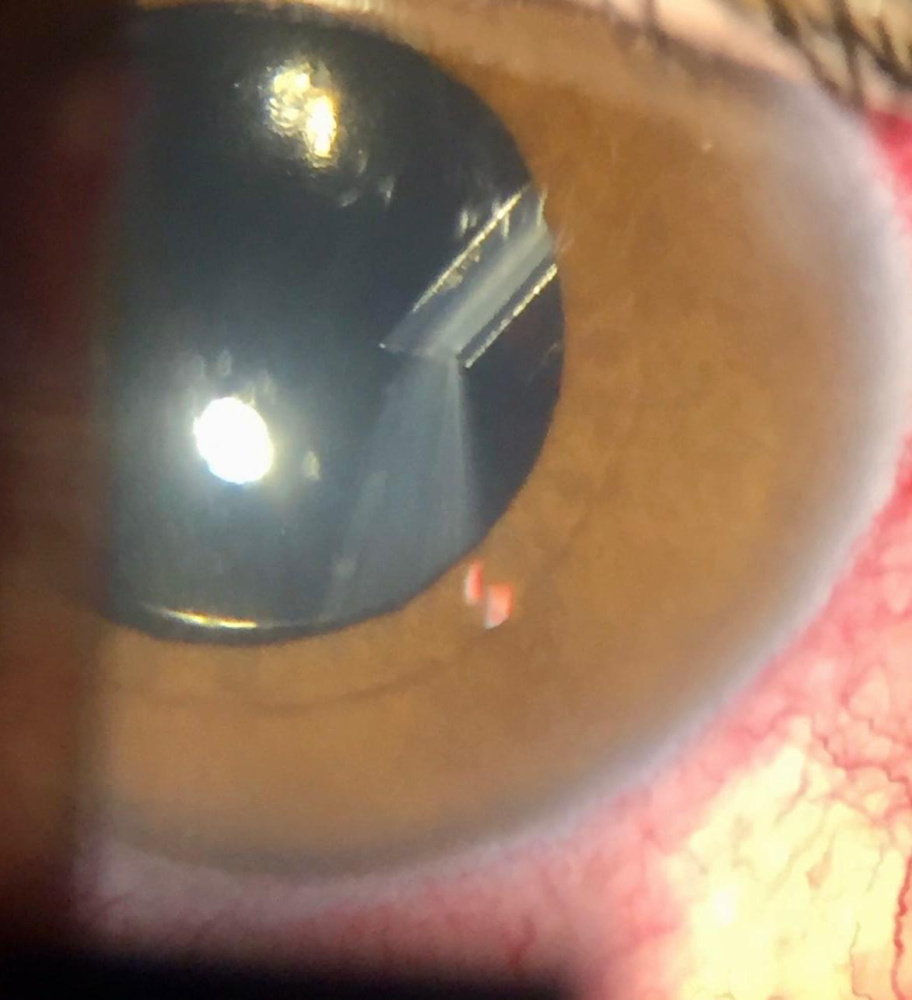

Título: Turning Up the Pressure: Here Comes ICE

Autor: Ana Mendes-da-Silva

Coautores: Ana Margarida Sampaio, Marta Vaz Pereira, Álvaro Silva, Marina João

Instituição: ULS Braga

Descrição: 37-year-old woman referred for suspected glaucoma, showing multiple nodular iris nevi, corectopia, and a closed angle in the right eye, diagnosed with iridocorneal endothelial (ICE) syndrome, Cogan-Reese variant.

Título: Turning Up the Pressure: Here Comes ICE Autor: Ana Mendes-da-Silva Coautores: Ana Margarida Sampaio, Marta Vaz Pereira, Álvaro Silva, Marina João Instituição: ULS Braga Descrição: 37-year-old woman referred for suspected glaucoma, showing multiple nodular iris nevi, corectopia, and a closed angle in the right eye, diagnosed with iridocorneal endothelial (ICE) syndrome, Cogan-Reese variant.